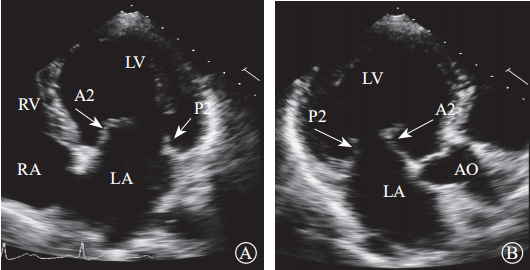

通过采集以下切面显示二尖瓣瓣叶各扇叶。(1)胸骨旁左心室长轴切面,显示A2、P2(图5A);(2)二尖瓣水平短轴切面,显示整个前后叶(图5B);(3)心尖四腔心切面,显示A2、P2(图6A);(4)心尖长轴切面,显示A2、P2(图6B);(5)心尖二腔心切面,显示A1、P3(图7A);(6)心尖二尖瓣交界处长轴切面,显示P1、A2、P3(图7B)。经胸超声心动图通过上述切面评价MR的机制、程度以及部位,并确定瓣膜运动异常的扇叶。

注:LA,左心房;LV,左心室;RA,右心房;RV,右心室

图 6 经胸二维超声心动图显示二尖瓣瓣叶各扇叶 A. 心尖四腔心切面,显示二尖瓣前叶 A2 处、二尖瓣后叶 P2 处;B.心尖长轴切面,显示二尖瓣前叶 A2 处、二尖瓣后叶 P2 处